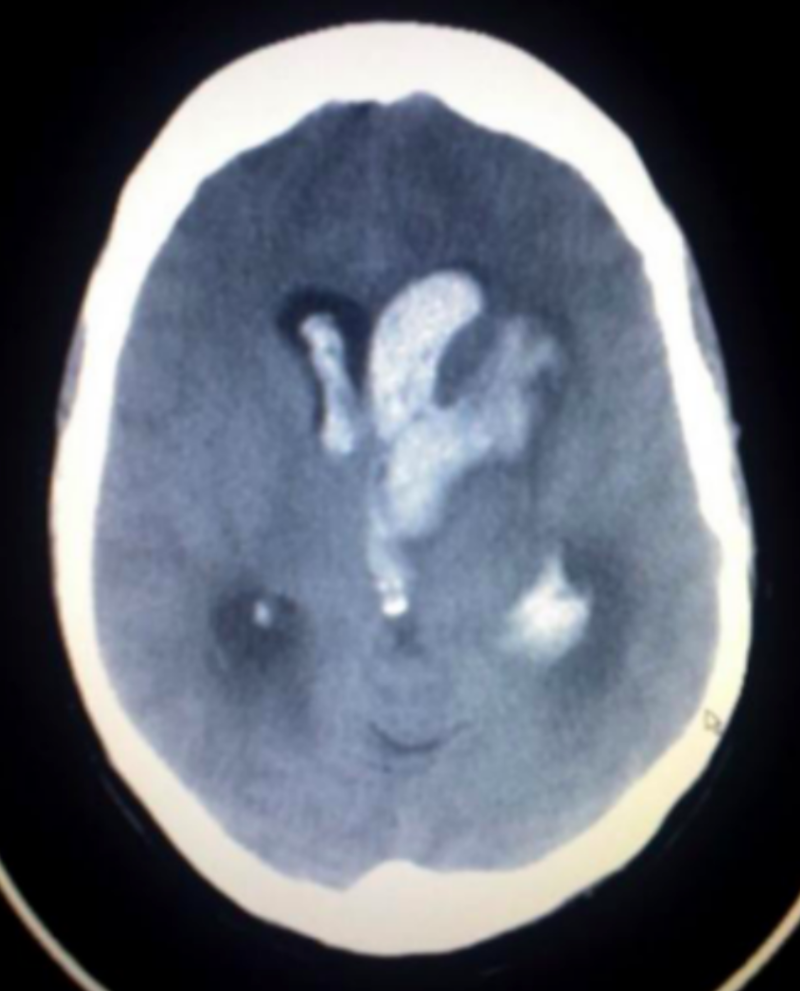

不看不知道,CT 显示患者有非常明显的大片脑出血以及脑水肿表现,正常脑组织已经受压,「看样子是要开急诊手术了。」

颅内出血 CT 表现(非此病例)

图源:Wikipedia